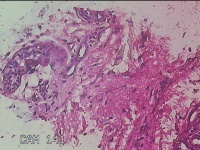

右足足底结节

性别

男

年龄

26岁

临床诊断

足滑膜囊肿

一般病史

患者于2年前,右足底异物刺伤后,出现局部结节,伴隐痛不适,无发热。

标本名称

大体所见

灰白粉红色梭形皮肤结节1.5x0.8x0.5cm一个,表面糜烂,切面灰白粉红色,质中。